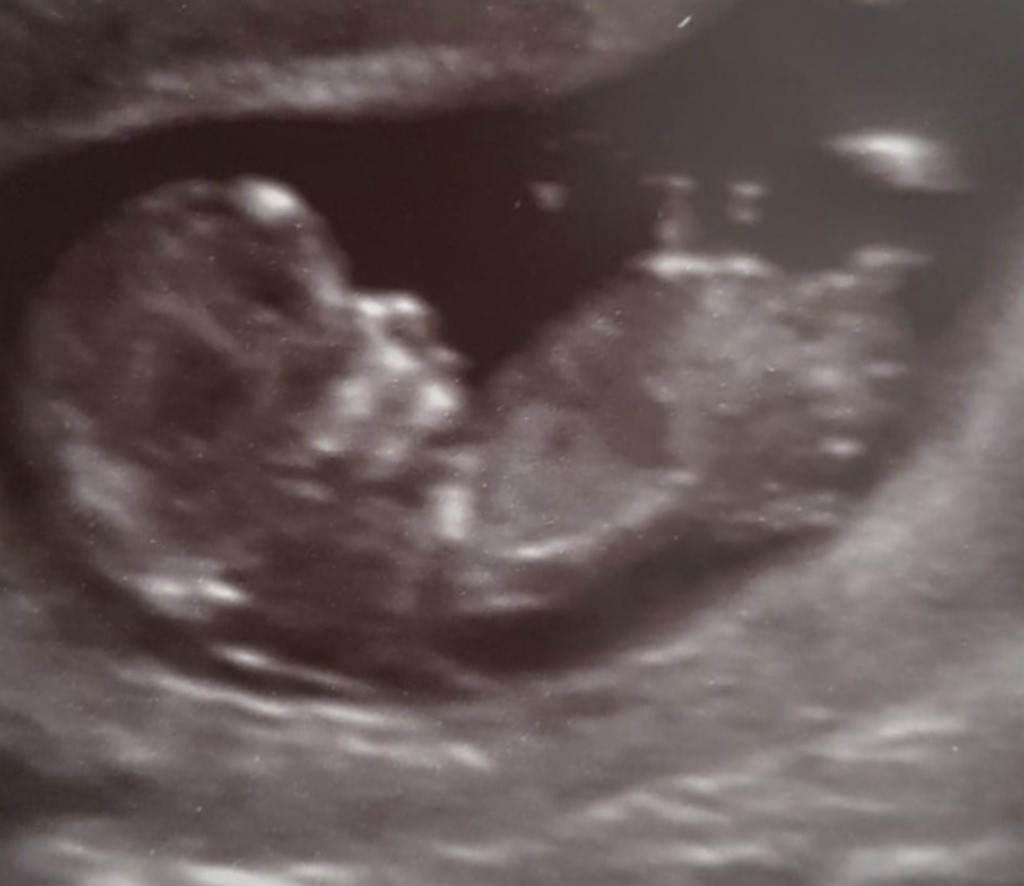

Jeg blev lidt inspireret af at se indlæg, hvor der er uploaded billeder fra nakkefoldscanningen, og der så er gættet på kønnet. Så har I lyst til at give jeres bud på dette billede

På forhånd tak og god weekend